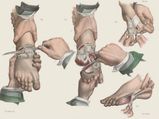

This Is How Surgeries Were Done In The Victorian Era